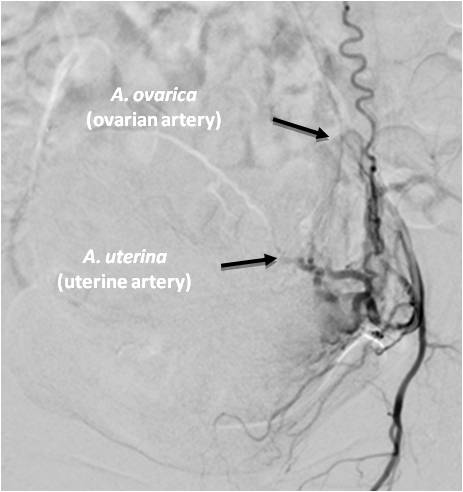

The uterine artery is usually a tortuous artery that is well visualized throughout its entire length (both the trunk and its small branches) (Figure 3).

Fig. 3. A selective angiogram of the left uterine artery after embolization of the uterine arteries: uterine-ovarian anastomosis.